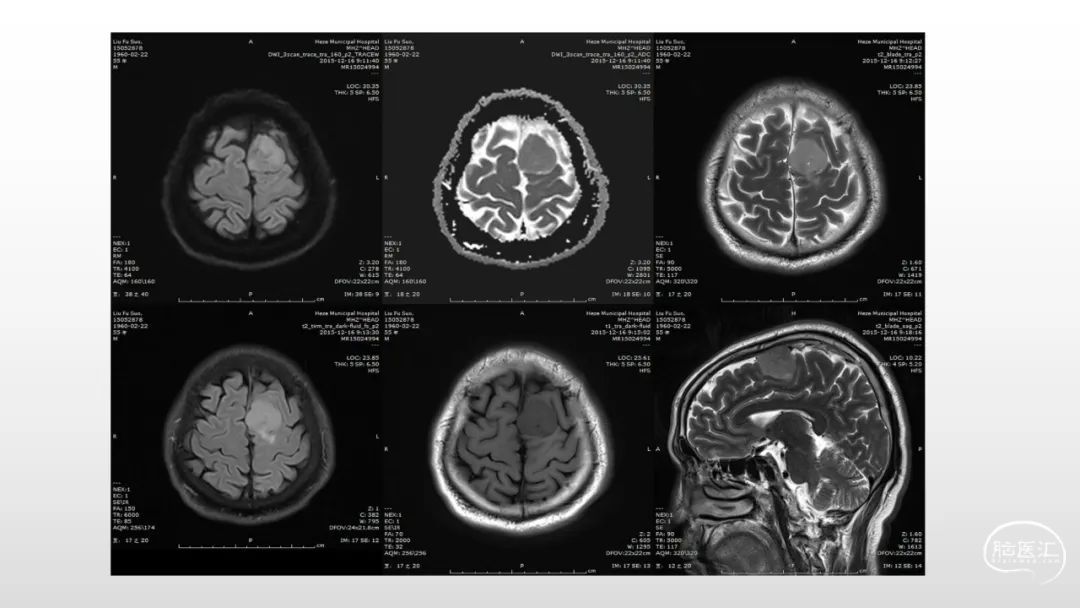

颅脑影像诊断基础知识讲座:脑膜病变